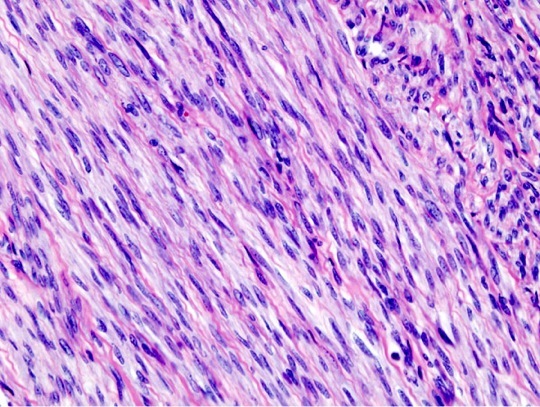

You get a biopsy of a suspected leiomyoma. What does this biopsy tell you about the prognosis?

The biopsy shows typical cigar shaped nuclei which could be seen in leiomyoma or in leiomyosarcoma, but the in the middle of the image there are 2 mitotic figures within one field, a very worrisome observation. This would be typical of a lower grade leiomyosarcoma. Worse prognosis than leiomyoma